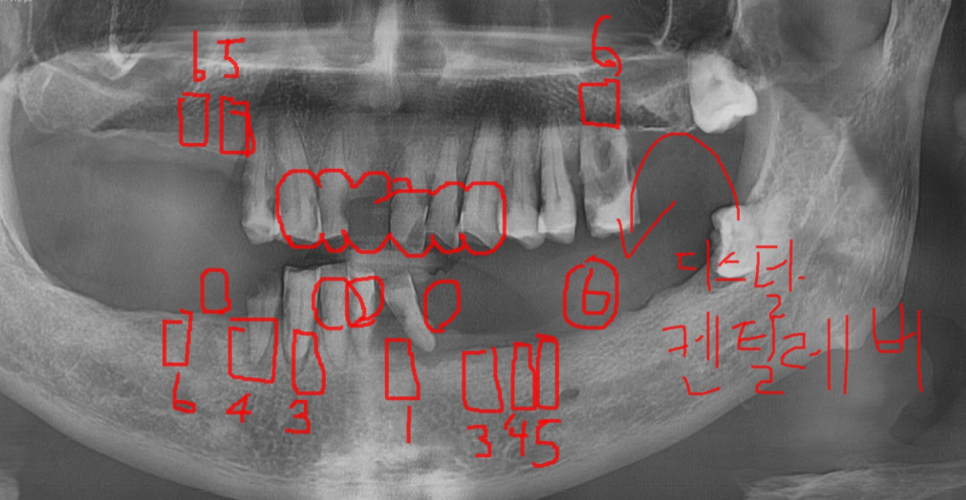

24014

뽑힌 치아도 많았고

앞으로 뽑아야 할 치아도 많았습니다.

상악은 그나마 괜찮았지만

아래 치아 같은 경우 하악 전체 임플란트가 필요했습니다. '

<치료 계획>

240502

분석과 고민 끝에 외국인 치과 진료 계획을 수립했습니다.

일반적으로 아래 치아 14개

위에 치아 14개 총 28개의 치아를 가지고 있습니다.

사랑니를 제외하고 말이죠.

모든 치아 개수를 충족해주는게 제일 좋지만

오늘 환자분처럼 치료 해야할 개수가 늘어나면

비용적 부담도 늘어나는 것이 사실입니다.

이럴경우 경제적으로

맨 끝 치아를 제외 하고 24개의 치아로 치료를 종결하곤 하는데요.

하악 전체 임플란트 7개 식립으로 12개의 머리를 만들고

상악은 상태가 안좋고 이미 뽑힌 치아만 임플란트로

나머지는 브릿지 치료로 진행하기로 상담해드렸습니다.